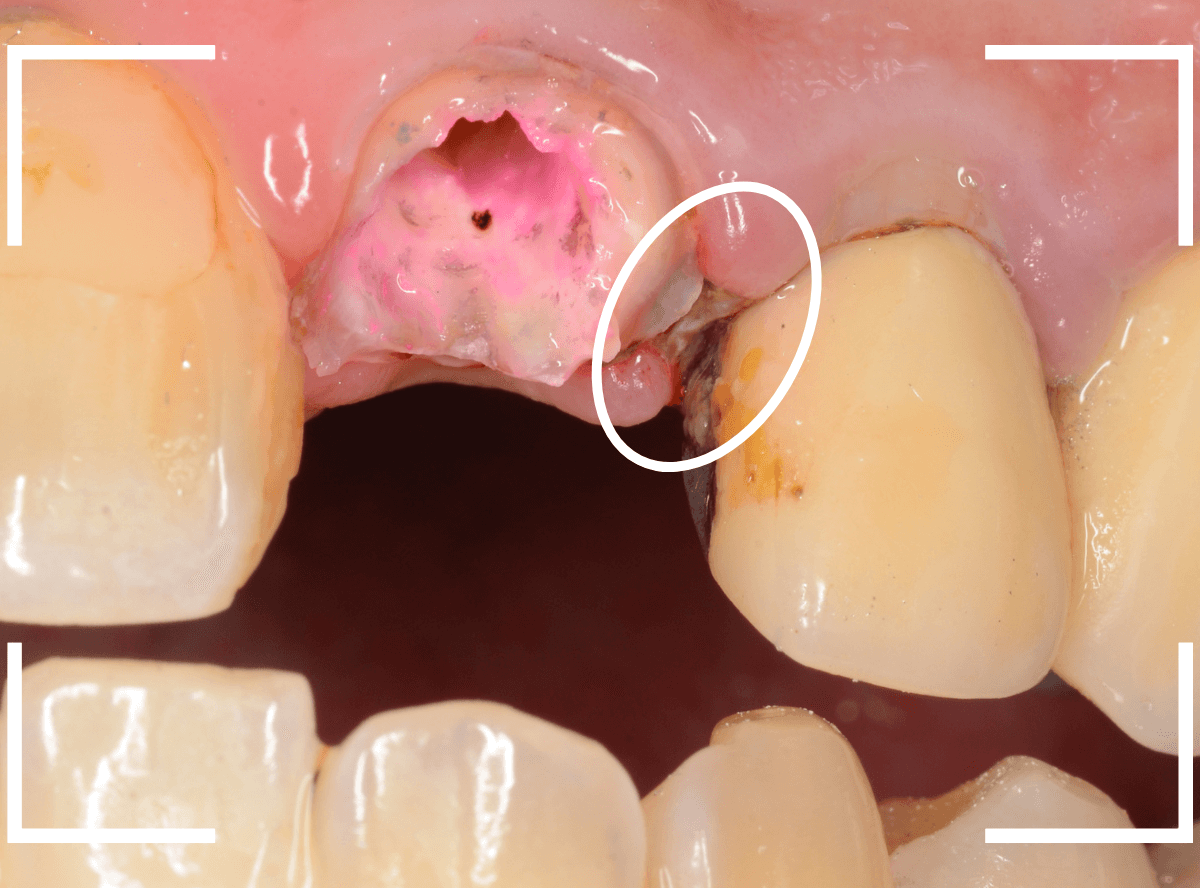

患者さんに状況を説明して、さし歯を外して確認します。

さし歯の中は、虫歯も進行しており、想像以上にひどい状況になっているのがわかります。

この状況では、いくら歯ブラシをしてもすぐにすき間に汚れがたまってしまうでしょう。

土台(メタル・コア)も外しつつ、虫歯を除去します。

赤く染色されている部分は虫歯です。

土台の中も虫歯になっていました。

早い段階で治療が出来てよかったです。

そして、後ろの歯との境の〇部には汚れや歯石が多くつまっています。

虫歯と共に、歯の周りの縁下歯石除去も行いました。

歯の周りがきれいになっているのがわかると思います。

隣のさし歯も、後日外して治療予定です。

このように、不適合なさし歯やつめものが入っている場合、それらを除去しないと、歯周治療がうまく進まない場合があります。